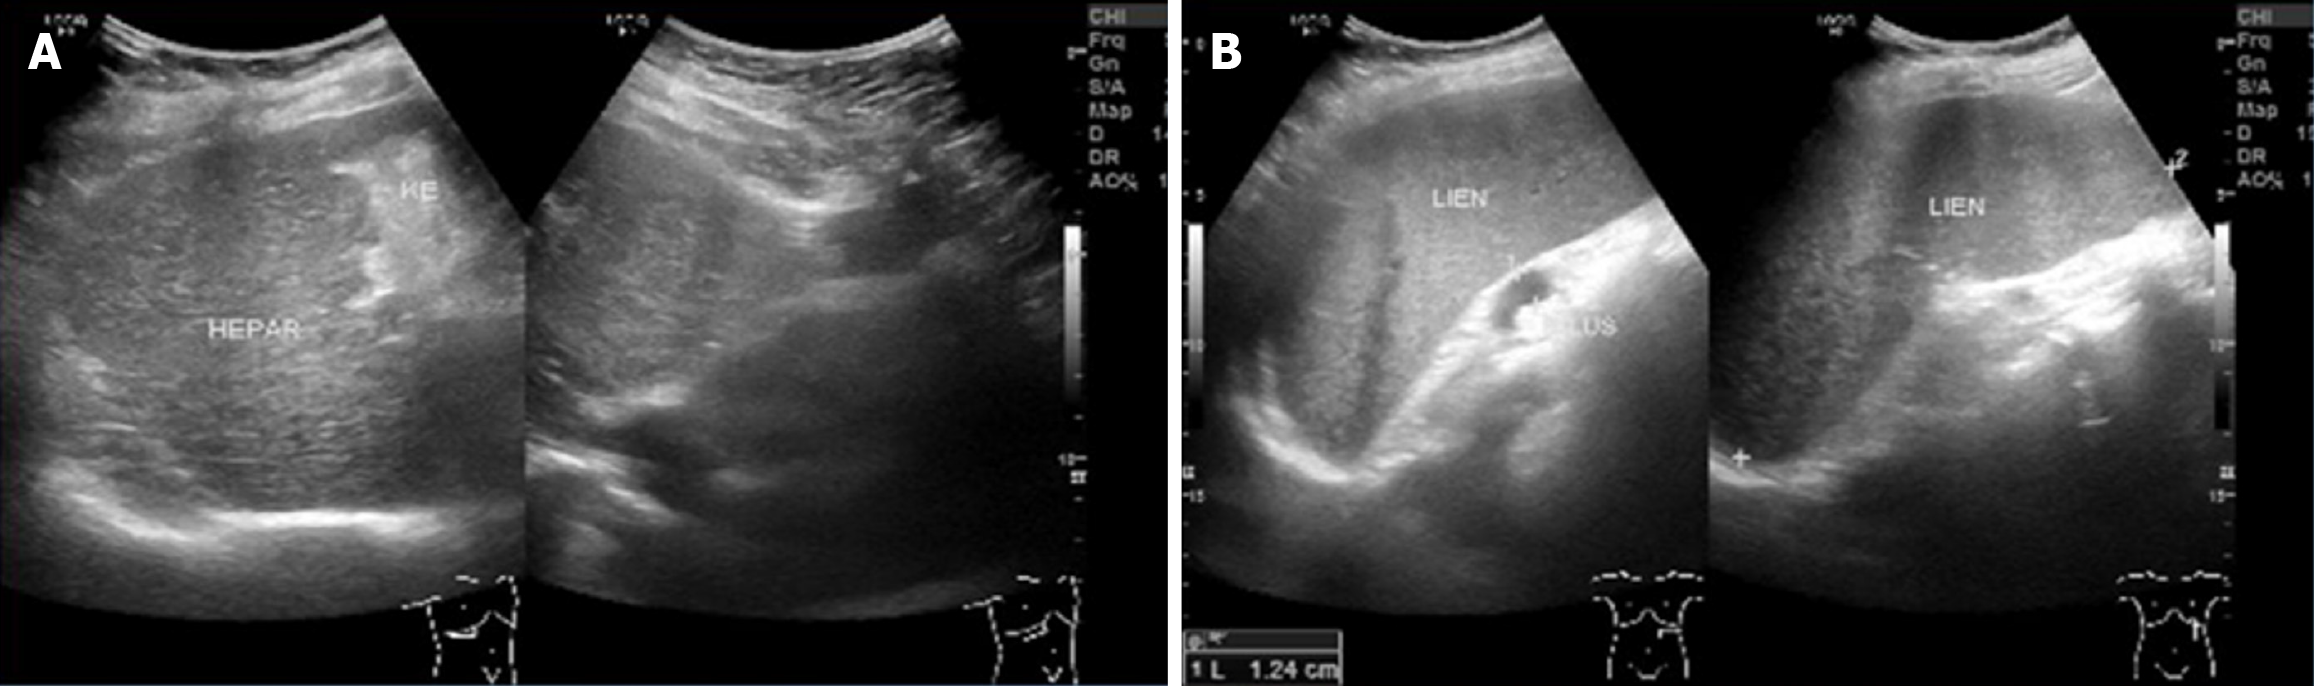

Figure 1 Abdominal ultrasound.

A: Right lobe liver (hepar), showing coarse hepatic echotexture consistent with chronic liver disease; B: Spleen (lien) showing splenomegaly with measurement 12.4 cm.